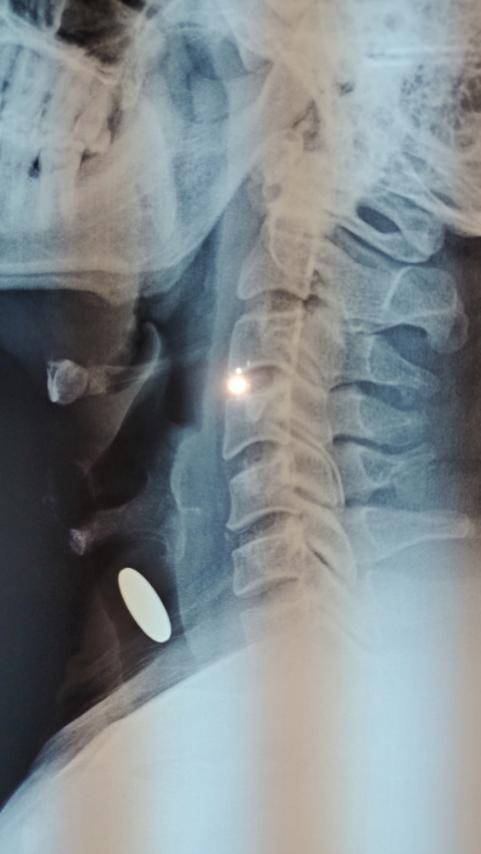

Tối 25-4, lãnh đạo Bệnh viện Đa khoa tỉnh Khánh Hòa cho biết, Khoa Ngoại Lồng ngực vừa phối hợp cùng khoa Tai Mũi Họng của bệnh viện đã phẫu thuật cấp cứu thành công cho bệnh nhân nam, 36 tuổi tại TP. Nha Trang do hóc dị vật là đồng xu rơi vào khí quản.

Trước đó, tối 24-4, bệnh nhân đang đùa giỡn, chơi trò tung hứng đồng xu với con mình, tình cờ khi ngước nhìn và há miệng cười đồng xu rơi lọt vào họng và gây ra tình trạng khó thở. Người nhà lập tức đưa bệnh nhân vào viện, kết quả chụp X-quang và CT Scan cổ bệnh nhân cho thấy có mảnh dị vật cản quang đường kính khoảng 2cm trong khí quản ở vị trí vùng trước sống cổ. Trước tình trạng nguy hiểm của bệnh nhân, đội ngũ y, bác sĩ trực của bệnh viện lập tức hội chẩn và đưa ra quyết định mở khí quản cấp cứu thông khí đường thở, ngay sau đó phẫu thuật mở rộng để lấy đồng xu.